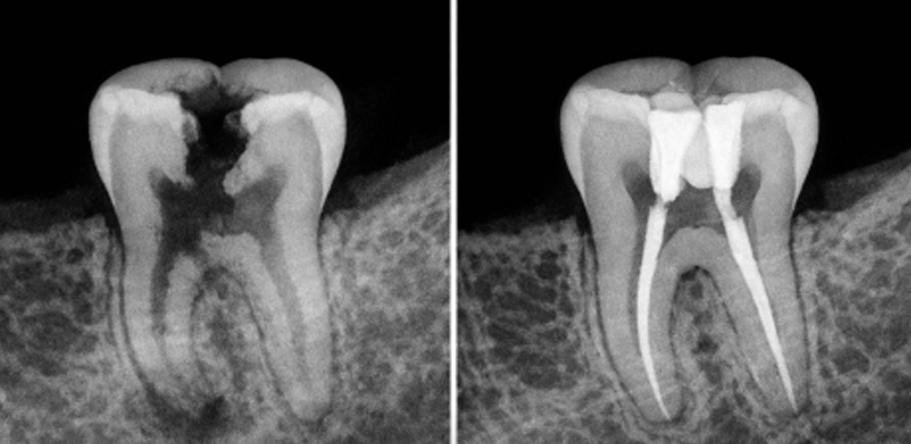

It’s a dental procedure designed to treat infections or damage inside a tooth. It involves removing the dental pulp (the soft tissue inside the tooth that contains nerves and blood vessels), followed by cleaning, disinfecting, and sealing the root canals. This treatment is recommended when the cavity is close to the nerve and is necessary when the pulp gets damaged or infected due to deep cavities. Its goal is to save the tooth and prevent it from being extracted.

The infection can worsen and spread to the surrounding bone or other parts of the body.

Delaying treatment may lead to more costly and complex procedures, such as implants or bridges. This treatment is recommended when the cavity is close to the nerve and the tooth can still be saved from extraction.